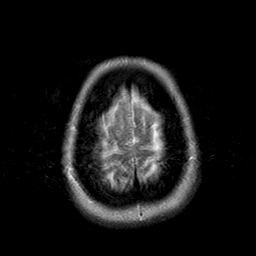

Cerebral hemorrhage, MR Study mr-t2 -- Slice #21

[Home][Help][Clinical] Slice 21